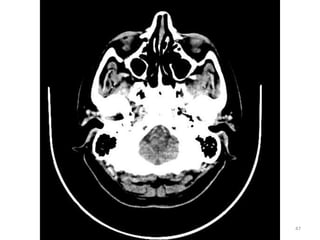

1. GLOBO OULAR (VITRIO)

2. FORAME MAGNUM

3. MUSCULO PITERIGÓIDE

MEDIAL

4. SEIO ESFENOIDAL

5. SEIO MAXILAR

6. ORELHA

1

2

3

4

5

6

ANATOMIA